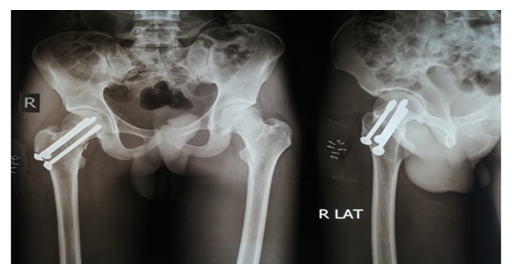

The screw lengths are measured, and drilling is performed using a 4.5 mm cannulated reamer. The screws are then inserted (for the BDSF technique, a specific sequence of middle, then superior, and lastly inferior screw insertion is to be followed). All three screws are inserted less than 5 mm subchondrally (Figure 3,4). In all cases, a prophylactic antibiotic was given. In the postoperative ward, proper fluid and hemodynamic balance were ensured. Change of posture was done twice an hour. The antibiotic was continued for 3 days. Analgesics were given to ensure a pain-free postoperative period. On the first postoperative day, patients were allowed to sit on the side of the bed. Patients were being educated about breathing exercises, isometric quadriceps exercises, gluteal exercises, and ankle pumping exercises. An immediate postoperative X-ray was done (Figure 5). After checking the dressing, on 4th POD, they were discharged from the hospital if their postoperative period was uneventful. Oral antibiotics were given for 10 days. Advice was given to continue isometric quadriceps exercise. Regarding ambulation, they were advised to do non-weight-bearing (of the affected side) crutch ambulation until directed by the physician. Use of elevated toilet seats onwards is also advised. The next follow-up would be given at the 14th POD. The first follow-up was given at 14th POD to check any signs of infection, pain status, and distal neurovascular status. The stitch was removed on the same day. Advice given about isometric quadriceps exercise, active abduction, extension exercise, and stretching exercise of the hip joint. The next follow-up was the 6th week after the operation. The range of motion was tested. An X-ray was done to check callus formation. Improvements were noted. Partial weight bearing was given at this follow-up. Subsequent follow-up was given at 12 weeks and every 4 weeks until union has been achieved or at least 9 months (Figures 6-10).